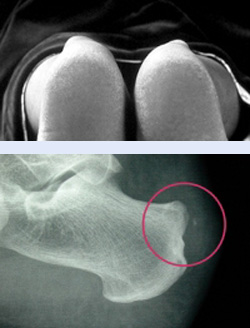

Zunächst beurteilt der Arzt Aussehen und Beweglichkeit des Fußes in einer klinischen Untersuchung. Die Vorwölbung der Haglundexostose ist meist mit bloßem Auge sichtbar. Häufig berichten Patienten zudem von starken Fersenschmerzen und Beschwerden beim Gehen, die dem Arzt weitere Hinweise liefern. Eine radiologische Untersuchung sichert die Blickdiagnose ab. Das seitliche Röntgenbild des Fußes zeigt einen deutlichen Knochenvorsprung (Überbein oder Exostose) im Bereich der Ferse. Mögliche Kalkablagerungen in der Achillessehne als Folge der Reizung sind ebenfalls im Röntgenbild sichtbar.

Um den Zustand der Weichteile wie Sehne und Schleimbeutel genauer einschätzen zu können, helfen zudem Ultraschall und MRT (Magnetresonanztomografie). Eine mögliche Schleimbeutelentzündung (Bursitis) wird hier sofort sichtbar.

Um das Krankheitsstadium festzulegen, bestimmt der Arzt außerdem den sogenannten Fowler-Philips-Winkel. Dieser Winkel ist bei einer Haglundferse deutlich vergrößert. Er wird anhand der seitlichen Röntgenaufnahme unter Belastung abgelesen. Für eine operative Behandlung streben wir einen Winkel von maximal 50° an.